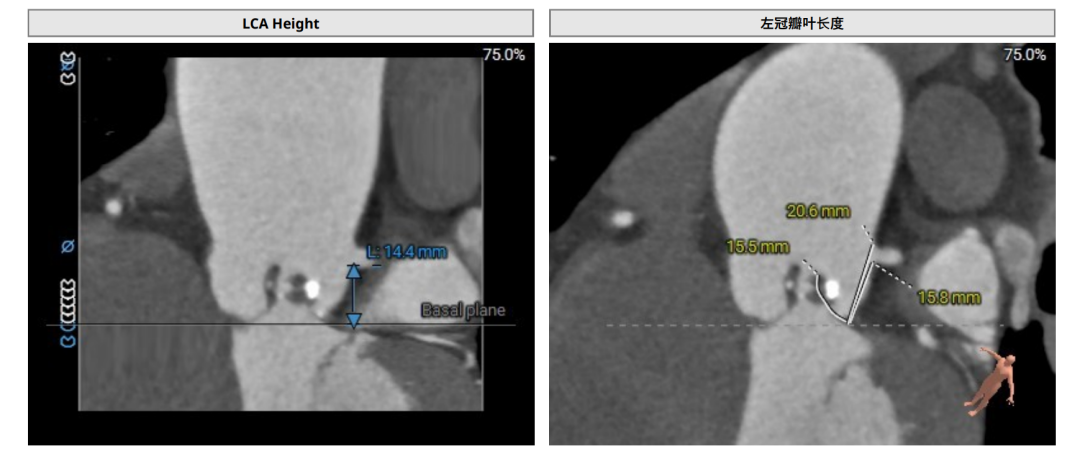

术前CT(上下滑动查看更多图片)

术中造影